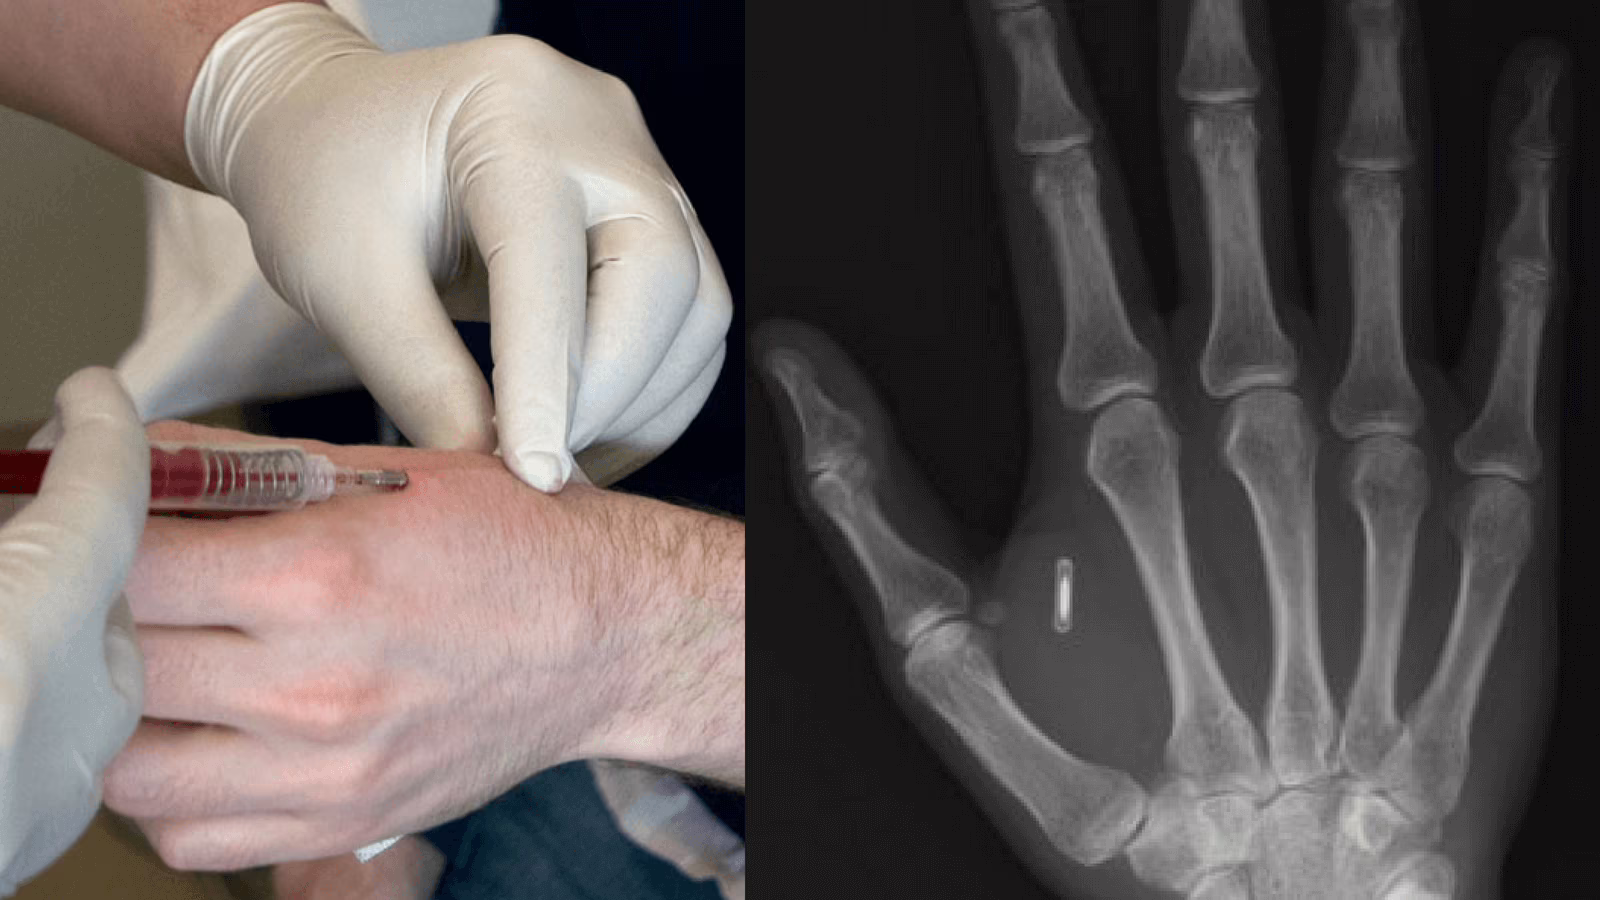

Con questa tecnologia forse già siamo entrati a far parte di un’era cyborg che poco si discosta dai film di fantascienza: grazie ad un microchip dal diametro più piccolo di una moneta, si diventa in grado di aprire le porte di casa e dell’ufficio, di pagare i propri acquisti al posto di utilizzare una normale carta di credito contactless, di convalidare i propri titoli di viaggio, di accedere a dispositivi digitali, di impostare un allarme e molto altro.

La scarsa diffusione di tali impianti su scala globale può farci pensare che le prime applicazioni di RFID siano recenti. Invece, il primo essere umano a ricevere un impianto di microchip RFID è stato lo scienziato inglese Kevin Warwick (soprannominato anche “Captain Cyborg”) nel 1998. Egli ha spiegato che lo scopo principale del “Progetto Cyborg” era quello di testare i limiti di ciò che il corpo umano avrebbe accettato e quanto sarebbe stato facile ricevere un segnale significativo dal microprocessore. Si trattava di una piccola capsula di vetro di circa 11mm di lunghezza per 1mm di diametro che racchiudeva un microchip e una bobina di antenna. Il chip non richiedeva una fonte di alimentazione interna; in alternativa, un’antenna incorporata nel chip utilizzava il campo magnetico di un lettore RFID per alimentarlo, permettendogli di fornire informazioni. Il chip inoltre poteva contenere un cappuccio di plastica per far sì che si attaccasse al tessuto umano e impedisse all’impianto di muoversi intorno al corpo.

Circa due decenni dopo il primo impianto, la tecnologia è stata resa disponibile al commercio e migliaia di persone hanno deciso autonomamente di farsi impiantare un chip con tecnologia RFID. Come precedentemente citato, questo chip potrebbe tornare molto utile in situazioni quotidiane, come sbloccare porte e auto, fino ad arrivare a situazioni di emergenza, in cui i soccorritori semplicemente scansionando la mano riuscirebbero ad avere l’accesso ai dati medici del paziente, velocizzando, così, le procedure.

Purtroppo, uno dei problemi più rilevanti di tali chip è la loro limitata capacità di contenere dati: quattro anni fa, un chip poteva memorizzare solo poco più di 1000 byte di memoria e non è aumentato molto nel corso degli anni. Il chip con tecnologia RFID è, inoltre, caratterizzato da una limitatezza dei compiti che sarebbe in grado di svolgere, costringendo il paziente a scegliere le mansioni a cui il chip dovrebbe essere adibito. Ciò comporterebbe l’utilizzo di molteplici impianti contemporaneamente. Al momento ha senso, ma in realtà ci aspettiamo che tali sistemi vengano aggiornati presto per funzionare con i chip RFID. Un altro problema riguarderebbe l’intromissione e l’accesso a dati sensibili da parte di hacker: alcuni biohacker affermano che è molto facile manomettere un impianto di questo tipo, come può accadere con telefoni e computer. Si parla di cyborgizzazione, perché rimuovere questi impianti non è facile come sembra, anzi si potrebbe addirittura affermare che sia più facile impiantarli che il procedimento contrario. Quindi si deve lavorare ancora molto su come renderne meno difficoltosa l’estrazione (basti pensare anche al caso di una semplice sostituzione per guasto). In conclusione, è possibile ordinare un chip RFID su alcuni siti internet, oppure provare presso alcune aziende, come la svedese Biohax International, che li ha resi notevolmente popolari nel paese scandinavo. Può questa tecnologia fare al caso nostro, in un mondo che diventa sempre più contectless?